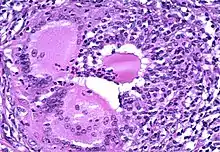

Microscopic image showing inflammation of the thyroid tissue

Thyroiditis is a group of disorders that all cause thyroidal inflammation. Forms of the disease are Hashimoto's thyroiditis, the most common cause of hypothyroidism in the US, postpartum thyroiditis, subacute thyroiditis, silent thyroiditis, drug-induced thyroiditis, radiation-induced thyroiditis, acute thyroiditis, and Riedel's thyroiditis.[5]